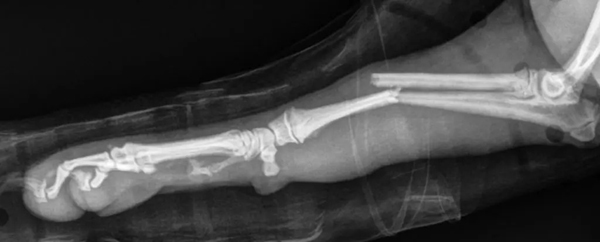

Test your veterinary knowledge with our monthly challenge, featuring a Pomeranian puppy presenting with right forelimb lameness.